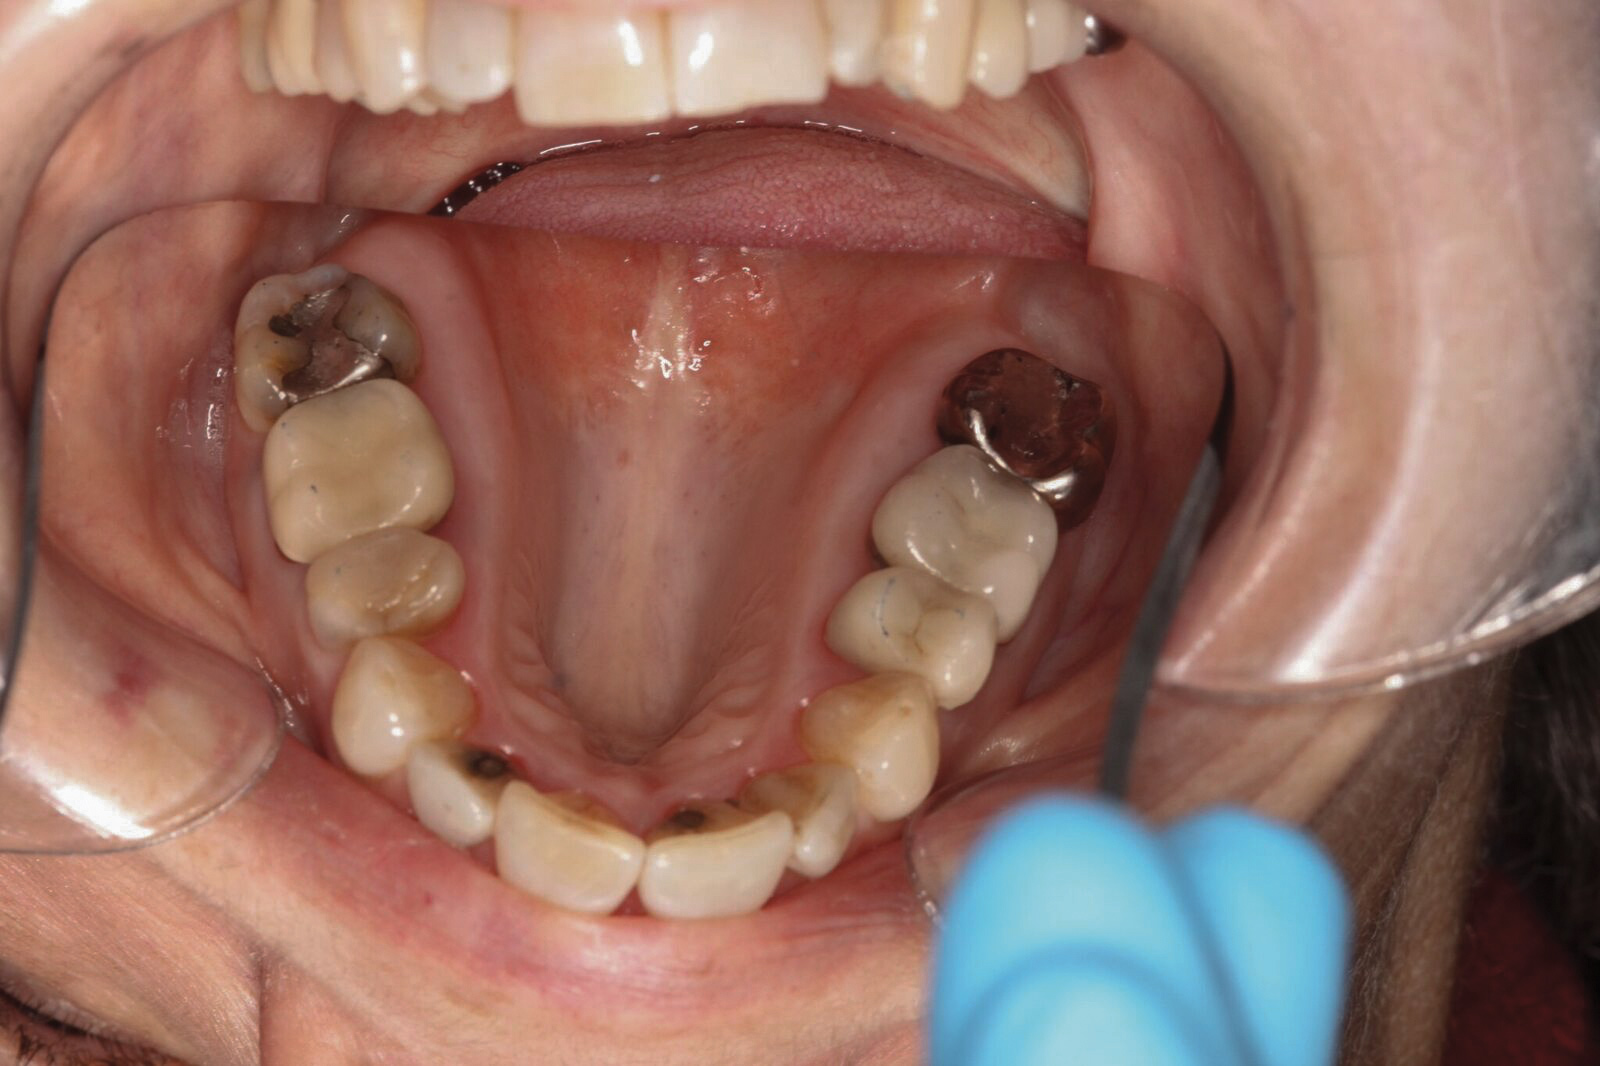

Dental sleep medicine (DSM) is a field in dentistry dedicated to the use and research of oral appliance therapy for the management of snoring and OSA. Oral appliance therapy is a noninvasive alternative to PAP therapy. Oral appliances fabricated by dentists with training in dental sleep medicine are commonly used to reposition the lower jaw forward to increase upper airway patency. Dental professionals have been recognized as being part of the multidisciplinary therapeutic team for the management of OSA because of their prime position of constant examination of the oropharyngeal areas. There are several oropharyngeal features contributing to the development of a narrow upper airway. These features are easily identifiable during a routine dental appointment, such as a large and scalloped tongue (Figure 1), narrow maxilla (Figure 2), small mandible (Figure 3), and retrognathic mandible (Figure 4). Combining clinical history intake, oropharyngeal examination, and the use of validated screening questionnaires, such as the STOP-Bang, dentists can screen for signs and symptoms of OSA and make recommendations for further diagnostic testing.

(3.) Small mandible with lingualized teeth.

Figure 3